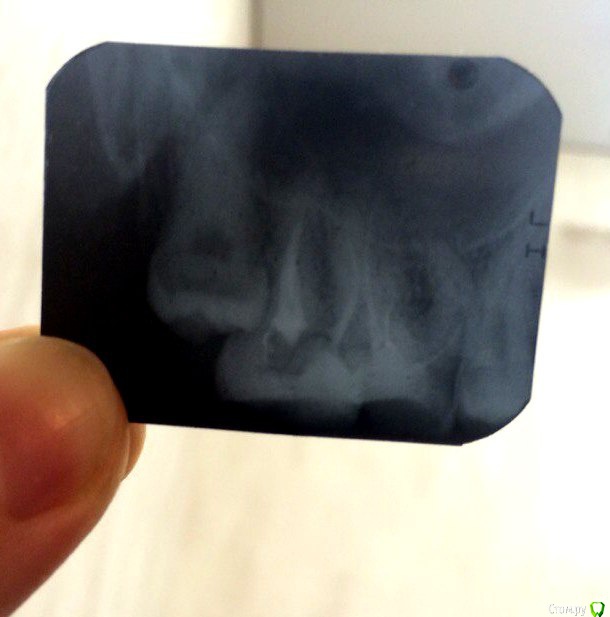

Elllenka Опубликовано 10 февраля, 2016 Поделиться Опубликовано 10 февраля, 2016 Добрый день!Хочу обратиться к Вам за советом.В конце ноября на рентген снимке врач случайно обнаружила кисту над шестым зубом и предложила его пролечить.Поскольку мы с мужем планируем ребенка, решила не откладывать на потом и решить вопрос с зубом, хоть он и не болел, периодически ныл от долгого пережевывания твердой пищи, но я спасалась полосканием содовым раствором и не придавала данному беспокойству большого значения.Стоматолог открыла зуб, сказала, что он был покрыт резорцин-формалиновой пломбой. Сообщила, что зуб внутри абсолютно черный, отметила, что она давно такого не видела, нервы умерли и каналы совершенно пустые. Промыла хлоркой и положила какое-то лекарство, закрыла временной пломбой, назначив следующую встречу через неделю. Спустя неделю она отправила меня на рентген и, увидев свежий снимок, сказала, что все отлично кисты нет, на ее месте восстановилась кость и можно смело пломбировать каналы. Я еще про себя удивилась - неужели за неделю может вырасти костная ткань. Врач каналы запломбировала, поставила постоянную пломбу.Спустя пару недель зуб начал меня беспокоить, боль не резкая и не острая, словно распирающая внутри челюсти, чувствуется легкое онемение внутри кости, усиливается при смыкании зубов. Ночью мне становится легче. Слизистая нормальная, розовая, припухлости и воспаления нет. Возникает и проходит боль самопроизвольно.Пришла с жалобой на беспокойство к врачу. Ответ, что на снимке все отлично, болеть ничего не должно и не может. Высказала предположение, что это зуб мудрости может давать такую боль. Но восьмерка меня не беспокоит и болит именно 6 зуб.Обратилась к другим специалистам. И вот тут мнения расходятся:1) дело не в восьмерке, а в недопломбированном изогнутом канале шестого зуба, его можно перелечить, распломбировать каналы и пройти их заново,2) дело в недопломбированном канале шестого зуба, но поскольку канал изогнут - он непроходим, следовательно нужно зуб удалить. Перелечивание с микроскопом - выкачивание денег, эффекта не даст (цитата).3) и лечение 6-го зуба возможно! только при использовании микроскопа. Прошу прощение за долгий рассказ.Очень надеюсь на Ваше мнение, советы. Потому что я уже третий месяц мучаюсь с болью и не знаю кому верить. Ссылка на комментарий